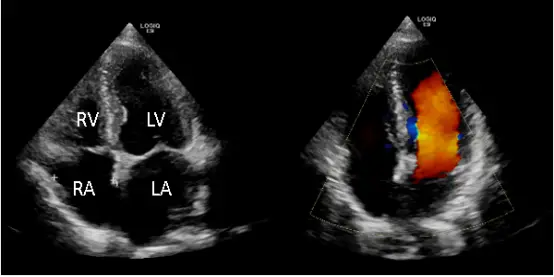

心脏彩超(心脏超声、心脏B超) 是利用超声波成像来观察心脏结构和功能的一种检查方式。

它能动态显示心腔大小、心肌厚度、心脏收缩舒张情况以及血液流动情况。

心脏彩超 = 给心脏做“实时动态录像”,医生能直接看到心脏在跳动。

✅ 心脏彩超:无创、安全、实时动态,全面评估心脏结构与功能